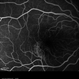

- retinal pigment epithelium

- Imaging device

- Scanning laser ophthalmoscope